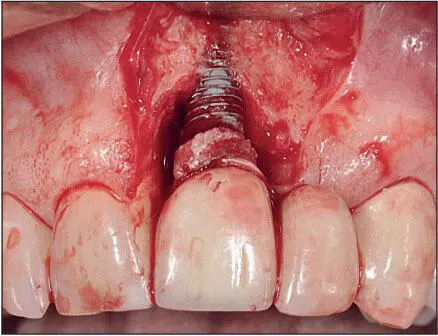

The titanium–soft tissue interface appears to be similar to but not exactly the same as that seen between gingiva and natural dentition ( Fig 1-7). The epithelial-implant interface is based on the hemidesmosome basal lamina system, similar to that seen between gingiva and teeth. When implants emerge through attached keratinized mucosa, collagen fibers circumferentially configured around the neck of the implant are interwoven with collagen fibers running from the crest of the alveolus and the periosteum to the free gingiva and hold the epithelium in close proximity to the surface of the implant. The epithelial cells in the sulcus epithelium secrete a sticky substance (a protein network of glycoproteins) onto the surface of the implants, enabling the epithelial cells to adhere to the implant surface via hemidesmosomes. The epithelial cuffs that form as a result of the basal lamina hemidesmosomal system and the zone of connective tissue just apical to it effectively seal the bone from oral bacteria. 29However, what differentiates the soft tissues around implants from the gingival tissues around natural teeth is the absence of gingival fibers inserting into a cementumlike tissue. Hence, the soft tissues around implants are more easily detached from the surfaces of the implant than are the soft tissues surrounding natural teeth. This difference is clinically significant for a number of reasons, including the manner in which these tissues respond to the oral microflora, 29and especially when cement systems are used for retention of implant prostheses because of the risk of embedding cement subgingivally during cementation of the prosthesis 30thereby increasing the risk of peri-implantitis 31( Fig 1-8).

Fig 17 Soft tissueimplant interface Fig 18 Periimplantitis triggered by - фото 11

Fig 1-7 Soft tissue–implant interface.

Fig 18 Periimplantitis triggered by excess cement beneath the periimplant - фото 12

Fig 1-8 Peri-implantitis triggered by excess cement beneath the peri-implant soft tissues. The bone loss has compromised the periodontal support of the adjacent teeth. (Reprinted from Moy et al 3with permission.)